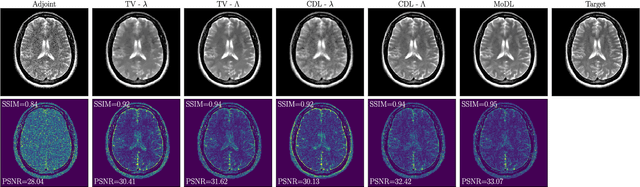

Abstract:We propose an unrolled algorithm approach for learning spatially adaptive parameter maps in the framework of convolutional synthesis-based $\ell_1$ regularization. More precisely, we consider a family of pre-trained convolutional filters and estimate deeply parametrized spatially varying parameters applied to the sparse feature maps by means of unrolling a FISTA algorithm to solve the underlying sparse estimation problem. The proposed approach is evaluated for image reconstruction of low-field MRI and compared to spatially adaptive and non-adaptive analysis-type procedures relying on Total Variation regularization and to a well-established model-based deep learning approach. We show that the proposed approach produces visually and quantitatively comparable results with the latter approaches and at the same time remains highly interpretable. In particular, the inferred parameter maps quantify the local contribution of each filter in the reconstruction, which provides valuable insight into the algorithm mechanism and could potentially be used to discard unsuited filters.